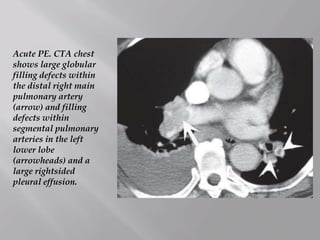

Acute PE. CTA chest

shows large globular

filling defects within

the distal right main

pulmonary artery

(arrow) and filling

defects within

segmental pulmonary

arteries in the left

lower lobe

(arrowheads) and a

large rightsided

pleural effusion.